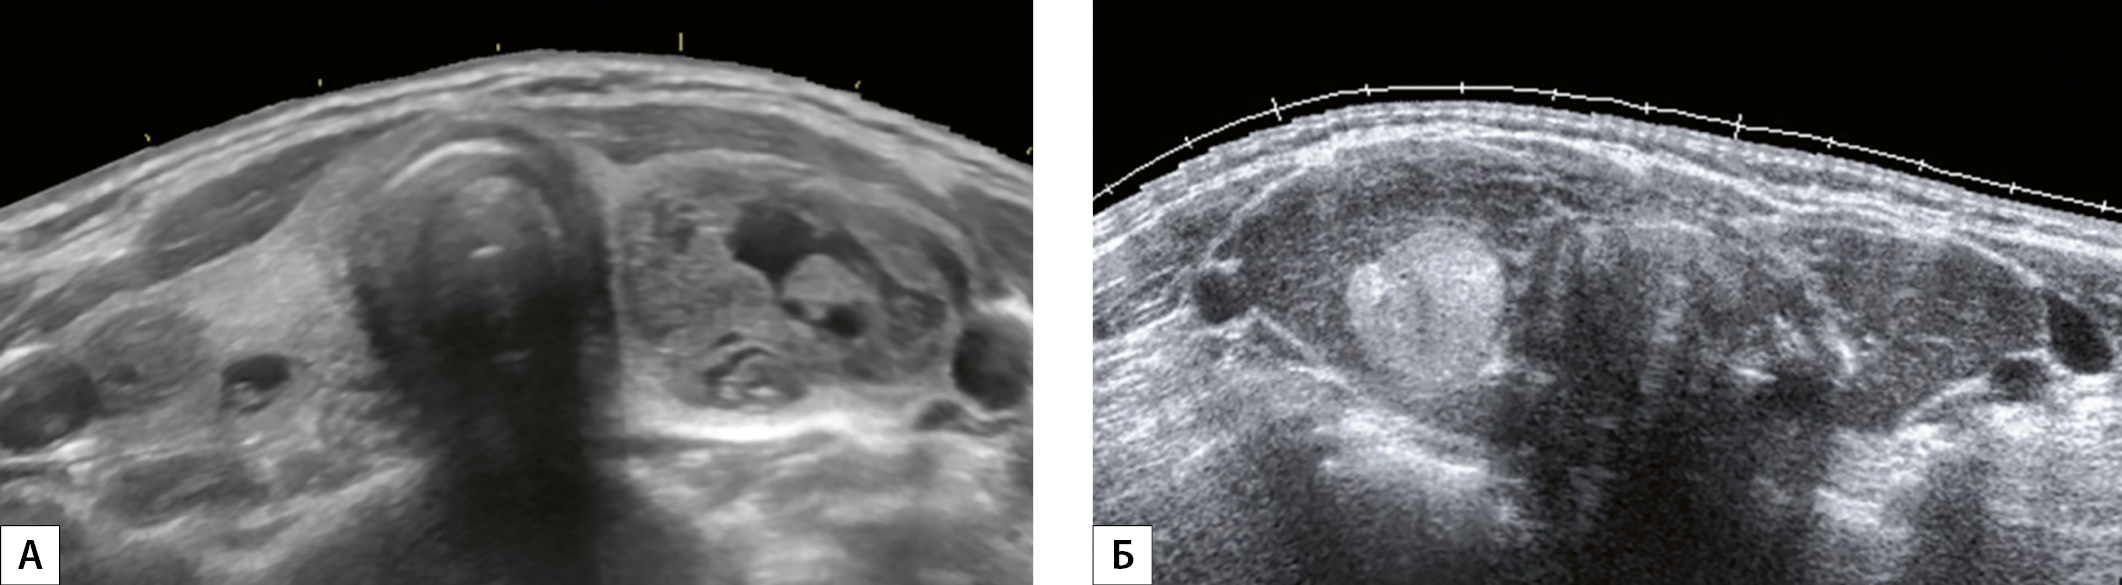

3. Рисунок 3. Эхограммы ЩЖ, выполненные в поперечной плоскости по методике панорамного сканирования на уровне среднего сегмента (перешейка). А — женщина, 45 лет, объем ЩЖ составляет 146 см³ и превышает верхнюю границу нормы в 8,1 раза. Б — женщина, 45 лет, объем ЩЖ — 33,9 см³, превышает верхнюю границу нормы в 1,8 раза.